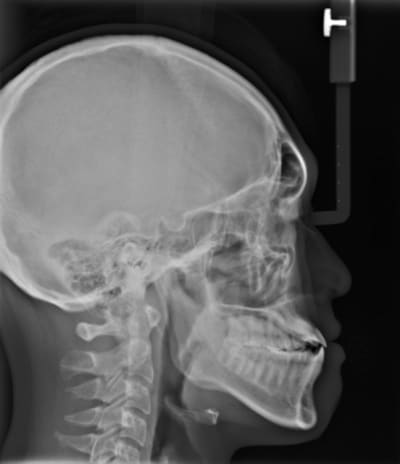

Ci joints photos, ceph, modeles.

Le gros défaut de ses deux options c'est que tu dois rétrocliner et faire une rétrusion des incisives maxillaires ce qui d'après la céph va se traduire par :

- résorption de l'apex des incisives ( qui semblent déja avoir une racines courte

- récession de l'os alvéolaire en palatin et vestibulaire.

il y'a une forte compensation alveolaire maxillaire superieure anterieurement et lateralement,

Une question, les analyses et la prevision faite sur la radio, sont faite pour un type caucasian ou asiatique????

Ils ont utilisé une analyse adapté au patient.

Ensuite ça dépend des populations tu a les normes pour coréen, japonais, Thai du nord et Thai du centre , chinois ect ect. A priori la population la mieux suivit en Asie c'est les japonais ils rétablissent leur nomes tout les dix ans.

On a des mesh et des normes pour :

-Caucasiens

-Afro américains

_Asiatiques

-Latinos

Le mesh utilisé ici est un asian mesh.

Par ailleurs ce n'est pas une prévision finale du traitement, c'est une aide au dignostic à base de normes préétablies de positionnement des points de repères.